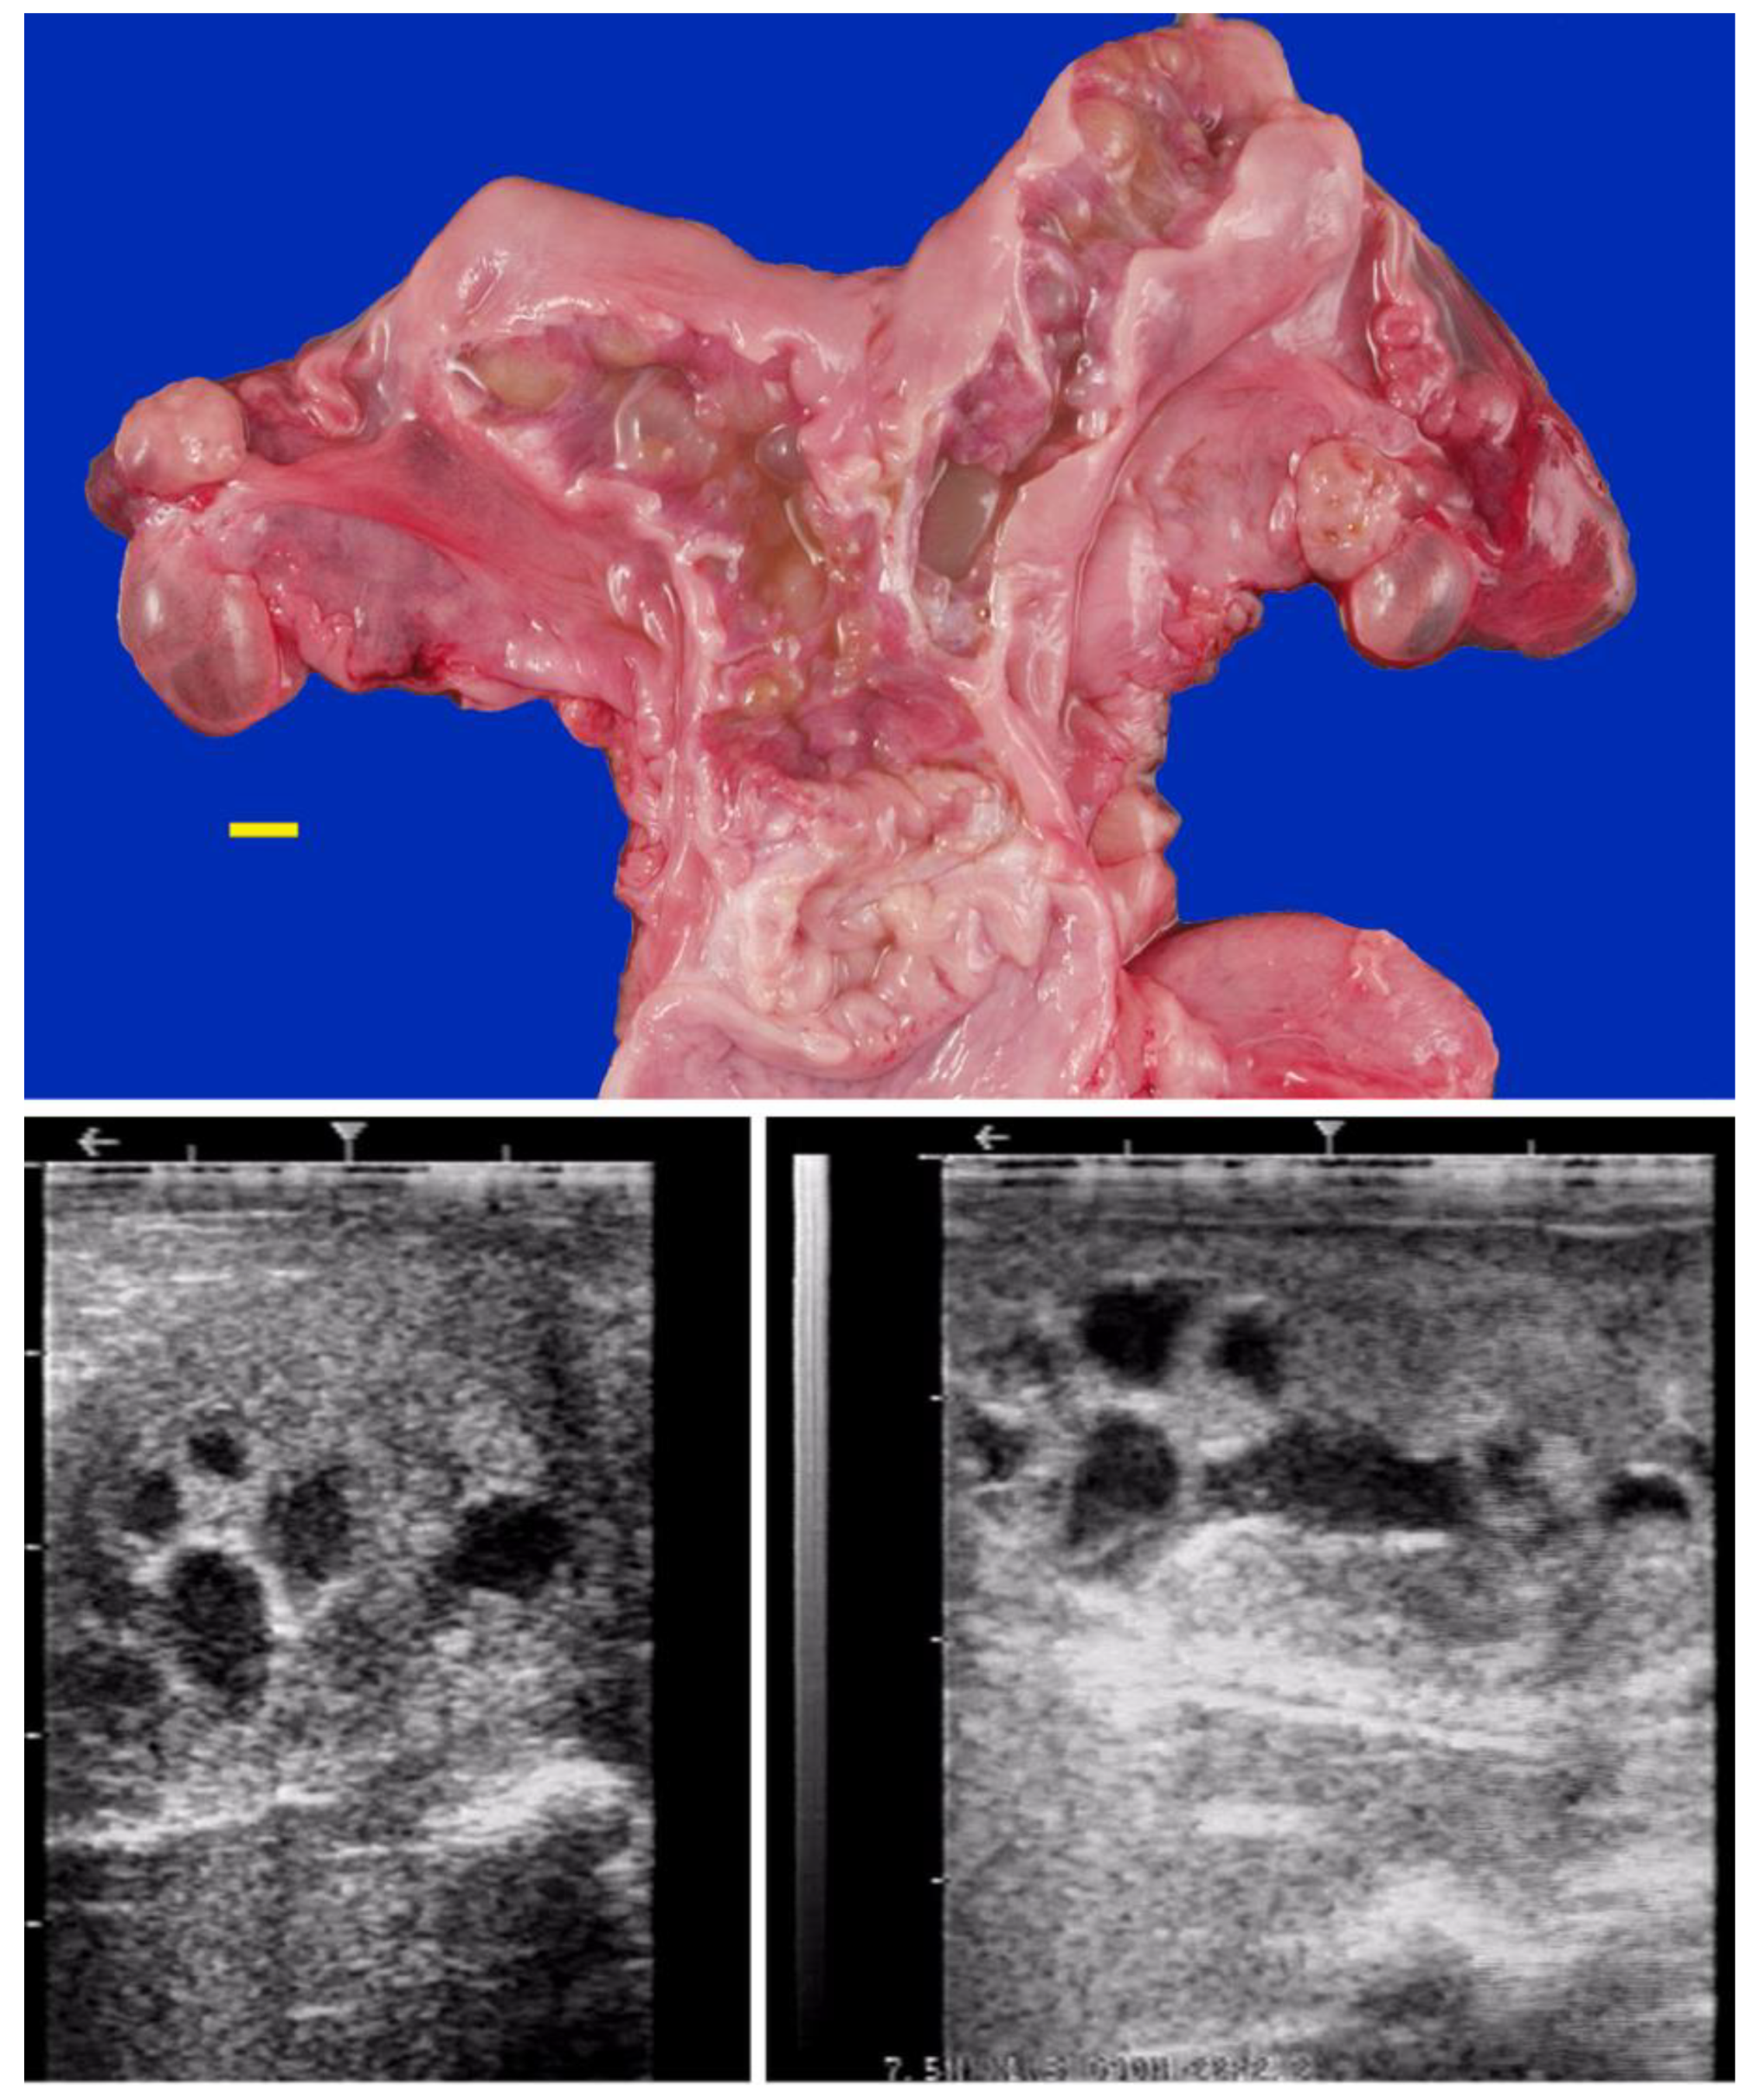

Hydrobursitis, or ovariobursitis, is a peculiar disorder in camels characterized by the accumulation of varying amounts of fluid within the ovarian bursa [80]. This pathology has been reported worldwide but appears to have a higher incidence in the Middle East [16,27,47,55,60,80]. The etiopathogenesis remains unclear. However, based on biochemical analysis of the fluid content, in some cases, the cause is attributed to recurrent ruptures of hemorrhagic follicles [10,80]. A variety of bacteria have been isolated (Actinobacillus spp., Escherichia coli, Klebsiella pneumoniae, Pseudomonas aeruginosa, Staphylococcus spp., and Streptococcus spp., as well as others) [5,10,18]. More recently, Chlamydophila abortus (Chlamydia abortus) infection has been demonstrated in several cases of hydrobursitis [17]. The role of Chlamydia spp., Brucella spp., and Campylobacter spp. in this pathology merits further investigation. Clinically, hydrobursitis is suspected when uterine retraction is not possible despite normal size of the uterus and cervix. Confirmation is easily obtained by transrectal or transcutaneous inguinal ultrasonography (Figure 6). This condition appears to occur predominantly on the left side. Bilateral development is more frequent in females with long-standing infertility (more than 2 years) [80]. The main signs include repeat breeding, early embryo loss, and abortion [13,16,27,80]. Endometritis, uterine adhesions, and pyometra may also be diagnosed in cases of hydrobursitis [6,10,13]. Treatment with oxytetracycline (20 mg/kg IM for 7 days) combined with intrauterine infusion of metacresol sulfonic acid and formaldehyde solution was shown to be effective in restoring fertility if the lesion is small (<3 cm) [11]. Surgical excision of the affected side is the only treatment for large lesions (Figure 7) [80].

Figure 6. Ultrasonographic images of hydrobursitis in camels. (a) Arrow: echogenic fluid within the bursa; (b) Arrow: abnormal ovary contained in the fluid-filled bursa.

Figure 7. Gross appearance of ovariobursitis surgically exposed by flank laparotomy in a camel.